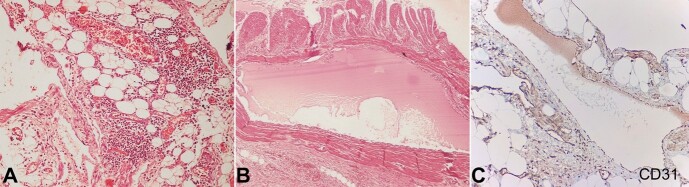

淋巴管瘤是一种罕见的良性肿瘤,主要累及儿童患者的头颈部。成人小肠系膜淋巴管瘤更为罕见。我们为大家介绍两例肠系膜淋巴管瘤患者,患者发病时伴有急性腹痛。病例 1:一名 38 岁女性,因腹痛、呕吐、发热和排便困难就诊。腹部检查时,她发现了一个界限不清、有触痛的肿块,放射学检查结果显示可能是穿孔性腹膜炎。因此,医生计划进行剖腹探查术。术中发现了一个肠系膜肿块,经组织病理学评估,发现这是一个累及肠系膜的淋巴管瘤。病例 2:一名 27 岁的男性因腹痛和排便困难前来就诊。放射学评估显示,病变累及肠系膜,可鉴别诊断为肠系膜纤维瘤和炎性假瘤。切除肿块的组织病理学评估显示,这是一种局限于肠系膜的淋巴管瘤。由于其罕见性和非特异性表现,肠系膜淋巴管瘤常常在临床检查和影像学检查中被误诊。因此,组织病理学检查是明确诊断的金标准。

Lymphangiomas are rare benign tumors that mainly involve the head and neck region in pediatric patients. Lymphangiomas of the small bowel mesentery in adults are rarer. We present two cases of mesenteric lymphangioma with acute abdominal pain on presentation. Case 1: A 38-year-old female presented with abdominal pain, vomiting, fever, and difficult evacuation. On abdominal examination, she had an ill-defined, tender lump, and radiological findings raised a possibility of perforation peritonitis. Thus, exploratory laparotomy was planned. Per-operatively, a mesenteric mass was found, which, on histopathological evaluation, was found to be a mesenteric lymphangioma involving the bowel. Case 2: A 27-year-old male presented with abdominal pain and difficult evacuation. Radiological evaluation revealed a multilobulated lesion involving the mesentery and with differential diagnoses of mesenteric fibromatoses and inflammatory pseudotumor. Histopathological assessment of the resected mass revealed a lymphangioma that was limited to the mesentery. Owing to their rarity and non-specific presentation, mesenteric lymphangiomas are often misdiagnosed on clinical examination and imaging. Thus, histopathological examination is the gold standard to reach a definitive diagnosis.